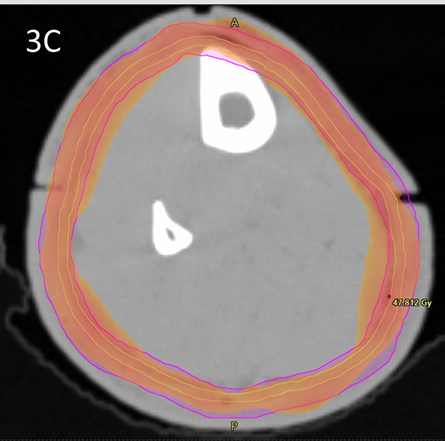

Wires were placed over all RO marks to capture these positions on the CT scan. The latter was done at 2mm increments. Bi-valved 3DPB was then ordered and was fitted at a second simulation session. The RO then contoured the clinical target volume (CTV) and planning target volume (PTV)8 according to the national protocol7 using MIM MaestroTM planning software. A contour volume called “Skin Avoid” was created by having a structure that extended on all the slices on which there was a PTV. This volume was made by the RO and was 1.5cm inside the PTV into the centre of the leg. The Skin Avoid structure was prescribed to receive a dose less than a mean of 25 Gy. See Figure 3.

Figure 3C Dosimetry with dose wash minimum set at 42.5Gy showing excellent conformality and homogeneity to the PTV.

Figure 3D Dosimetry with dose wash minimum set at 25Gy showing excellent avoidance of the skin avoid structure.

Figure 3 Contouring and dosimetry.